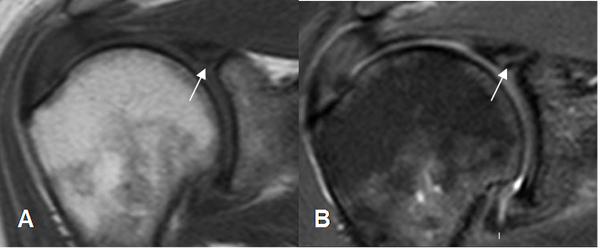

Fig 76. Lesión SLAP.

A: RM coronal en STIR y B: ArtroRM coronal en STIR. Defecto amplio en el labrum superior, por lesión SLAP, que se extiende al origen de la cabeza larga del biceps y confirmada en la ArtroRM.